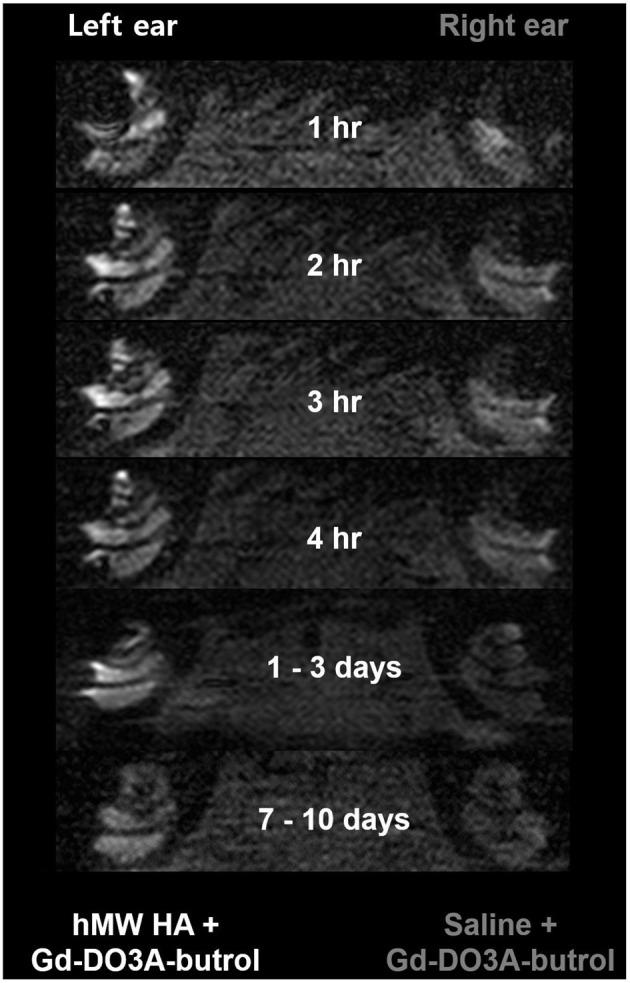

Intratympanic (IT) gadolinium (Gd) injection is one method of delivering Gd into the inner ear to evaluate the amount of endolymphatic hydrops (EH) using magnetic resonance imaging (MRI). As Gd is usually prepared in a fluid form mixed with saline, Gd injected into the middle ear drains easily through the Eustachian tube within several hours. High-molecular-weight (hMW) hyaluronic acid (HA) is an ideal vehicle for IT Gd due to its viscous and adhesive properties. The present study was performed to elucidate whether novel hMW HA is superior to conventional HA in delivering Gd into the inner ear in the short term. The second aim was to verify the long-term Gd delivery efficiency of hMW HA compared to the standard-of-care vehicle (saline). IT Gd injection and 3D T1-weighted MRI were performed in 13 rats. For the short-term study (imaging after 1, 2, and 3 h), the left ear was treated with hMW HA+Gd and the right ear with conventional HA+Gd. For the long-term study (imaging after 1, 2, 3, and 4 h, 1 - 3 days, and 7 - 10 days), the left ear was treated with hMW HA+Gd and the right ear with saline+Gd. Signal intensities (SIs) in the scala tympani (ST) and scala vestibuli (SV) were quantified. Compared to conventional HA, signal enhancement was 2.3 - 2.4 times greater in the apical and middle turns after hMW HA+Gd injection (SV at 1 h). In comparison to the standard-of-care procedure, the SI was not only greater in the short term but the higher SI also lasted for a longer duration. On days 7 - 10 after IT Gd delivery, the SI in the basal turn was 1.9 - 2.1 times greater in hMW HA+Gd-treated ears than in saline IT Gd-treated ears. Overall, hMW HA may be a useful vehicle for more efficient IT Gd delivery. Gd enhancement in the cochlea improved approximately two-fold when hMW HA was used. In addition, this greater enhancement lasted for up to 7 - 10 days. Repeated MRI of EH may be possible for several days with a single IT hMW HA+Gd delivery.

鼓室内(IT)注射钆(Gd)是将Gd输送至内耳以利用磁共振成像(MRI)评估内淋巴积水(EH)量的一种方法。由于Gd通常以与盐水混合的流体形式制备,注入中耳的Gd在数小时内很容易通过咽鼓管排出。高分子量(hMW)透明质酸(HA)因其粘性和粘附性,是IT注射Gd的理想载体。本研究旨在阐明新型hMW HA在短期内将Gd输送至内耳方面是否优于传统HA。第二个目的是验证与标准护理载体(盐水)相比,hMW HA的长期Gd输送效率。对13只大鼠进行了IT Gd注射和三维T1加权MRI检查。在短期研究中(1、2和3小时后成像),左耳用hMW HA + Gd治疗,右耳用传统HA + Gd治疗。在长期研究中(1、2、3和4小时、1 - 3天以及7 - 10天后成像),左耳用hMW HA + Gd治疗,右耳用盐水 + Gd治疗。对鼓阶(ST)和前庭阶(SV)中的信号强度(SI)进行了量化。与传统HA相比,hMW HA + Gd注射后,顶转和中转中的信号增强在1小时时(SV)是传统HA的2.3 - 2.4倍。与标准护理程序相比,SI不仅在短期内更高,而且较高的SI持续时间更长。在IT Gd给药后7 - 10天,hMW HA + Gd治疗组耳的底转SI比盐水IT Gd治疗组耳高1.9 - 2.1倍。总体而言,hMW HA可能是更有效地进行IT Gd输送的有用载体。使用hMW HA时,耳蜗中的Gd增强提高了约两倍。此外,这种更大的增强持续长达7 - 10天。单次IT hMW HA + Gd给药后,可能在数天内对EH进行重复MRI检查。